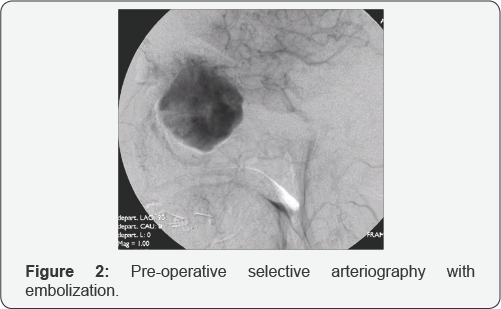

The control computed tomography with mean of contrast showed the hyper vascular fleshy mass with a volumetric increase (49 x 59 x 49mm) with respect to the previous exam. It had a multilobed aspect with the involvement of the whole nasal cavity, both ethmoidal labyrinths, both maxillary sinuses, the left frontal sinus and the sphenoid right one. The left lacrimal sac and the corresponding nasolacrimal duct appeared infiltrated, with a bilateral thinning of the lamina papyracea (Figure 1). A conventional angiography was performed to confirm the vascular nature of the tumor: a pathological flow from the branches of the internal maxillary artery and from the anterior and posterior ethmoidal arteries was noticed (Figure 2). A complete tumor embolization was performed with super selective catheterization of the internal maxillary artery with coaxial Rapid Transit® system, using four vials of 10 ml each of 500 micron microspheres. Np embolization of the ethmoidal arteries was carried out to avoid any risk of sight impairment.

Pre-operative examinations must include neuroradiological investigation to detect the vascular nature of the tumor and its extension. CT scans of the nose and paranasal sinuses can demonstrate bone involvement, and the intravenous mean of contrast infusion can show tumor enahancement, but it does not allow a clear distinction with inflammatory fluid [14]. Usually, MRI scan shows a solid isointense mass, with a strong enhancement after gadolinium on T1 weighted sequences. On T2 weighted imaging, HPCs appear isointense to low intense, while inflammatory fluids have high-intense signals [12]. The best visualization of the vessel supply of the SNTHPC can be achieved by conventional digital angiography, which helps at the same time to plan a preoperative embolization [15].

Substantial intraoperative bleeding during SNTHPC surgical removal may be a major problem in the management of these highly vascularized tumors. Traditional preoperative embolization by a transarterial approach has proved beneficial but is often limited by the complex vascular anatomy and unfavorable location of such tumors. In our opinion, preoperative direct intralesional injections of cyanoacrylate are recommended, especially in case of extended SNHPCs to avoid severe bleedings and reduce surgical time. Traditionally the open approach (lateral rhinotomy) with or without pre-operative embolization, was the usual technique for the resection of large SNTHPCs [10].